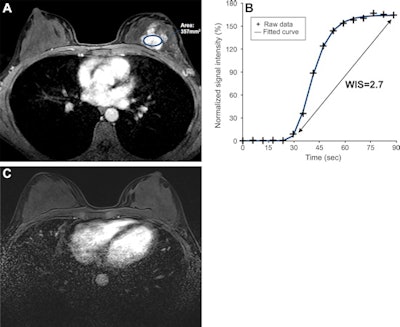

Researchers led by Dr. Toulsie Ramtohul from the Paris Sciences et Lettres Research University found that by measuring the slope between the time of contrast inflow onset and the time of peak intensity in breast tumors -- known as the wash-in slope -- clinicians can predict how tumors respond to neoadjuvant therapy with high sensitivity.

Previous research shows that one such parameter, the wash-in slope, is a predictor of aggressiveness in several cancers. Such slope depends on the peak height and time to peak for contrast agents, which reflect the perfusion flow rate and blood volume in tumors. However, these parameters have not been used to explore neoadjuvant chemotherapy in breast cancer treatment.

The team found that a wash-in slope cutoff value of 1.6% per second had a sensitivity of 94% (17 of 18 women) and a specificity of 59% (19 of 32 women) for complete pathologic response. Wash-in slope also was also the factor that was most associated with predicting complete pathologic response, as measured by hazard ratio.